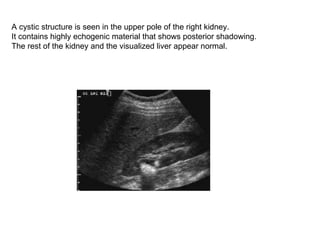

A cystic structure is seen in the upper pole of the right kidney.  It contains highly echogenic material that shows posterior shadowing.  The rest of the kidney and the visualized liver appear normal.